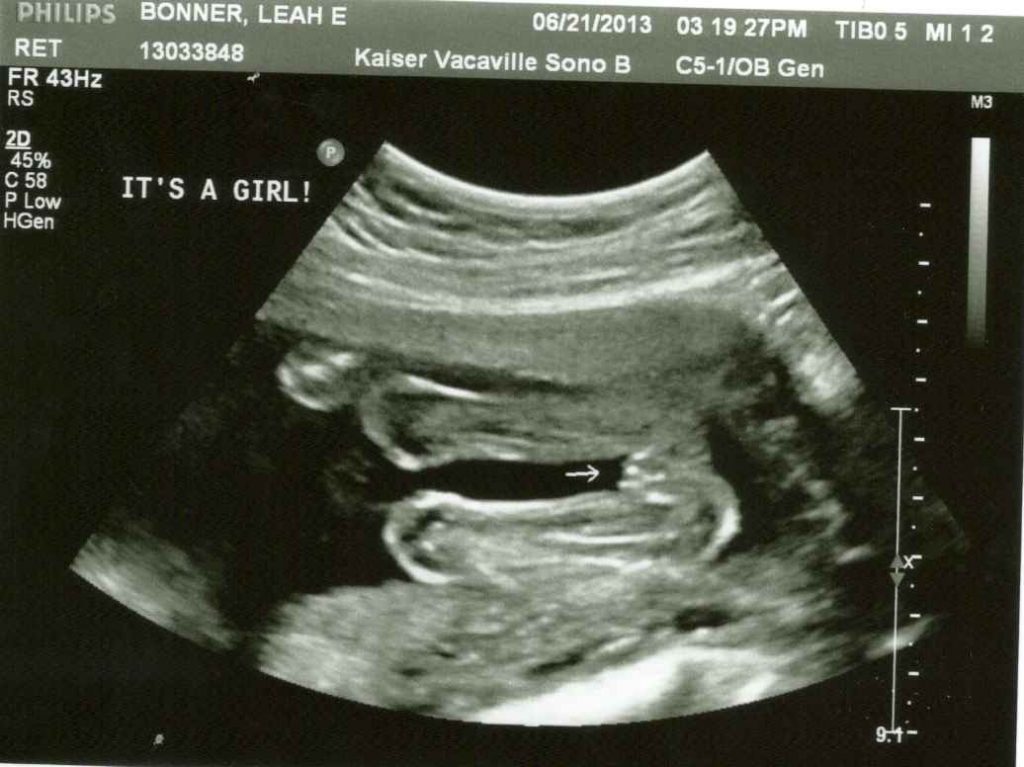

Фото Ребенка 20 Недель

Фото Ребенка 20 Недель 118 фотографий